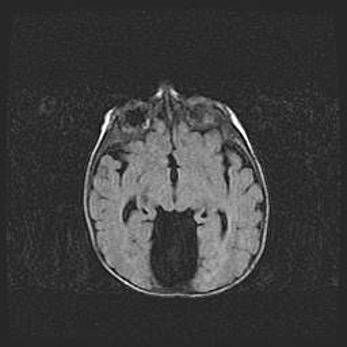

Сообщающаяся гидроцефалия. Кистозная энцефаломаляция головного мозга.

Возраст: 3 месяца 4 дня

Вес: 3100 г

Пол: женский

Окружность головы: 34 см

Срок гестации: 31 неделя

Кистозная энцефаломаляция головного мозга - одна из форм поражения головного мозга в детском возрасте. Характеризуется возникновением множественных и распространённых кист в коре, белом веществе и подкорковых образованиях головного мозга у плодов, новорождённых и детей раннего возраста. Развитие кистозной энцефаломаляции связано с внутриутробной асфиксией и гипотонией, родовой травмой, тромбозом синусов, пороками развития сосудов, инфекциями, сепсисом и другими причинами. Наиболее значимые инфекционные агенты: вирусы простого герпеса, цитомегалии, краснухи, токсоплазмы, энтеробактерии, золотистый стафилококк и другие.